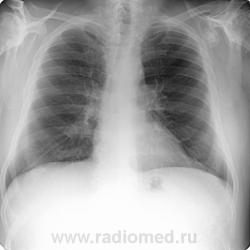

Пациент 60 лет, при прохождении проверочной флюорографии  обнаружены изменения со сторны плечевых суставов.Водитель троллейбуса.Страдает избыточной массой тела, люмбальгией, артороз коленных суставов.Непосредственно жалобы на плечевые суставы в медицинских документах не отражены. Какое будет мнение у коллег?

Александр, конечно надо доснять плечевые суставы... Из того, что есть: видимые отделы плечевых костей выглядят довольно симметрично, хотя слева и похуже, думаю - артроз. Весьма настораживает левая лопатка на предмет хондросаркомы

Уважаемый Александр, приходиться признать, что на цифровой рентгенограмме легких изменения плечевых суставов видны лучше, чем на "обрезаных" и недоэкспонированых снимках суставов. По имеющимся данным могу только сказать, что деф. артроз с кистовидной перестройкой структуры есть. Под хрящевой опухолью (возможно - хондросаркома) левой лопатки я имела в виду тень, отмеченую красными стрелками, которая в поле снимка не вошла. Моя вина - в силу специфики работы такие узкоформатные снимки давно были вредными, т.к. очень часто патология остается за пределами снимка. Остается рекомендовать рентгенография левой лопатки в прямой передне-задней и косой проекциях, а лучше - КТ...